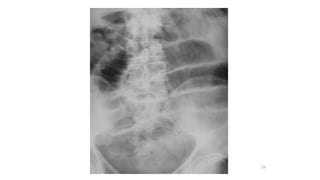

Abdominal radiographs

• 2 views are required which are Supine and Erect

• Small bowel lie centrally and colon peripherally

• Plain X-ray abdomen in the erect position may show

multiple gas fluid levels. Gas levels appear earlier than fluid level. Normally,

two insignificant fluid levels can be present, one in the terminal ileum and one in

the first part of the duodenum.

• Supine films indicate the distal limit of obstruction .